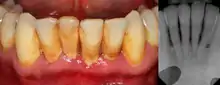

Periodontitis

The defining feature of periodontitis is connective tissue attachment loss which may manifest as deepening of periodontal pockets, gingival recession, or both. This loss of support for the teeth is essentially irreversible damage. Chronic periodontitis is generally slow to moderate in terms of disease progression, although short bursts of increased tissue destruction may occur. Ultimately, tooth loss may occur if the condition is not halted. It is termed localized when less than 30% of sites around teeth are involved, and generalised when more than 30% are involved. clinical attachment loss can be used to determine the severity of the condition, where 1-2mm is slight, 3-4mm is moderate and more than 5mm is severe.[5]